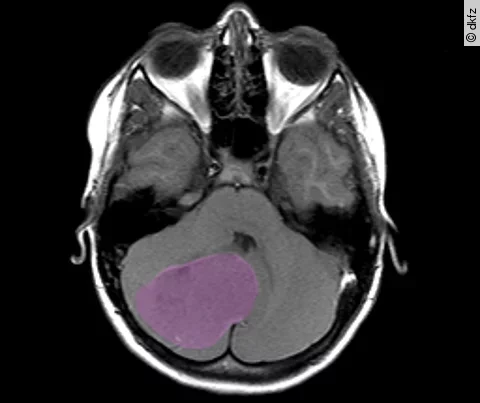

Medulloblastome können in jedem Lebensalter vorkommen, meistens jedoch treten sie bei Kindern auf. Kinder erkranken besonders häufig an Tumoren der Gruppen 3 und 4, die bislang wenig verstanden sind. Die Behandlung von Tumoren dieser Gruppe ist daher häufig schwierig.